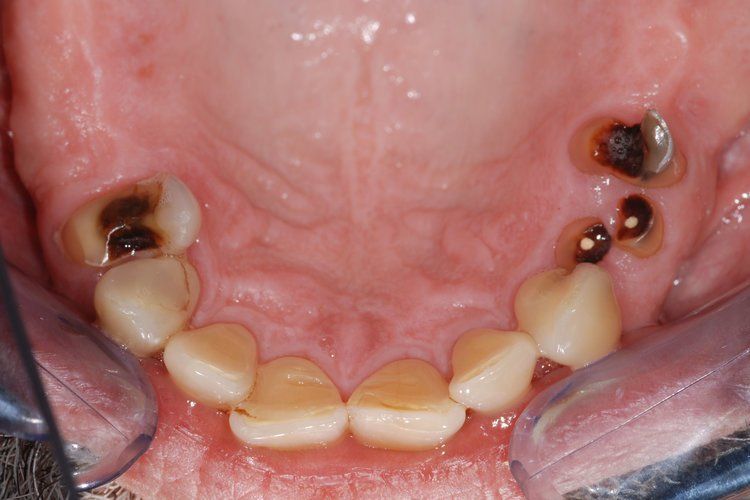

Unfortunately, it can be the case that a tooth (or teeth) are so badly damaged by trauma, bacteria, or tooth decay that removal is the only option. In this case, we recommend that a patient has dental implants inserted to replace any missing teeth. Modern dental implants are long lasting, strong, and look, feel, and function just like real teeth.

At the Dental Innovations clinic in Wasilla, AK, we specialize in single and multiple implant restorations. Our team can use a wide range of implant systems to provide patients with a full mouth of even, strong teeth. Contact our dental clinic today to arrange a consultation to discuss what dental implants may be the best for you.